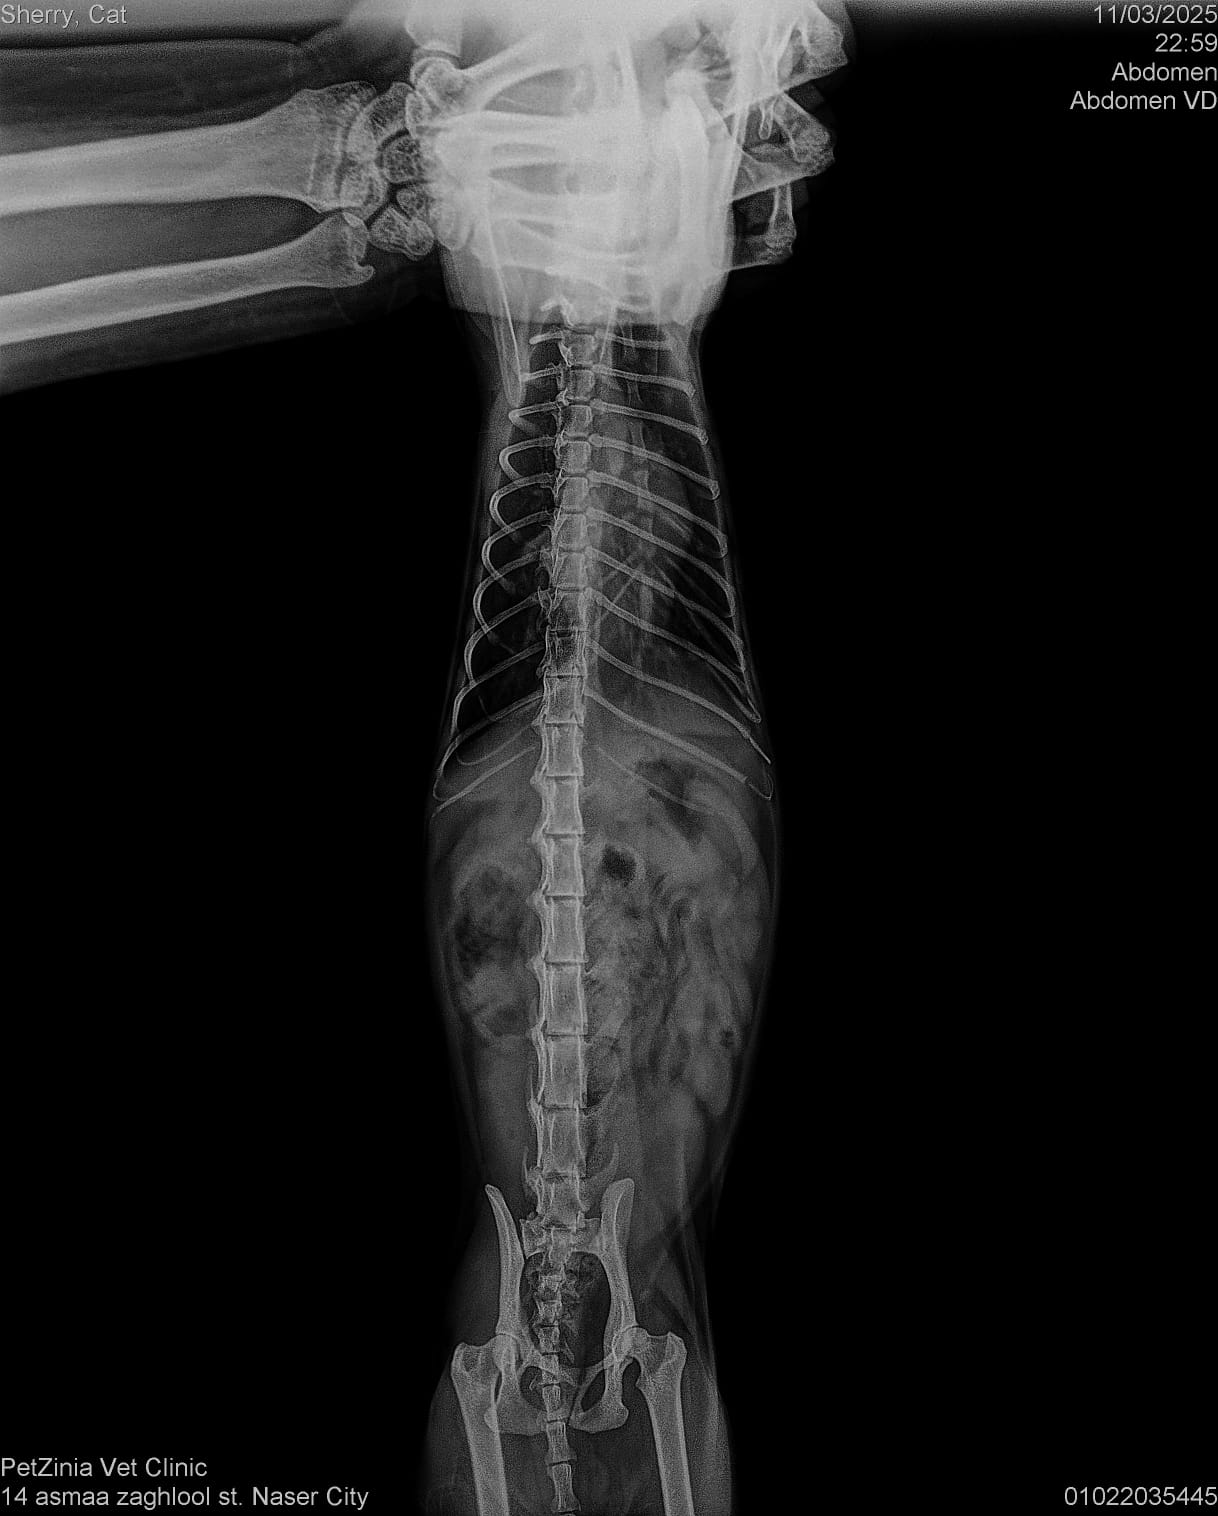

Taxi 6 months, Hit by a car and had a leg Amputation. Stayed more than 8 months at vet and then went to our kahu shelter to get his vaccines and the care need it